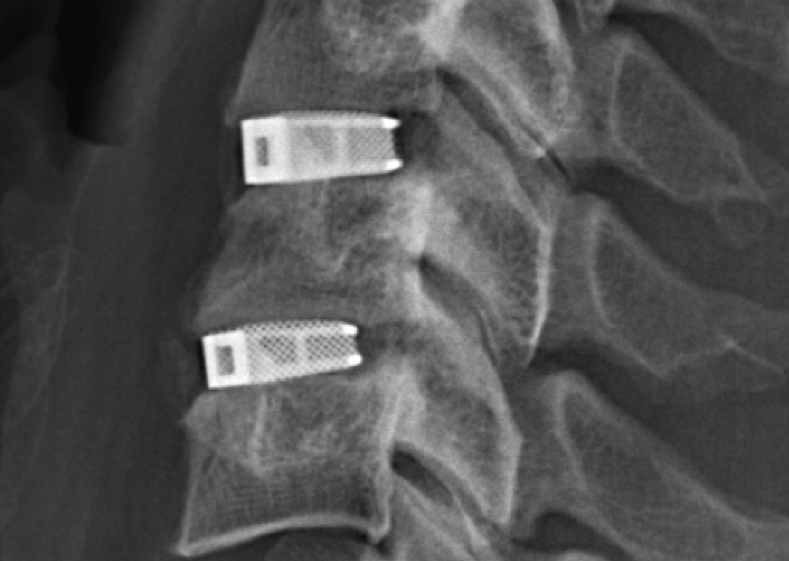

EIT Cellular Titanium implants are made using Selective Laser Melting (SLM), forming open and interconnected porous structures designed to promote bone in-growth. Last year, EIT’s Cellular Titanium implants received 510(k) clearance from the FDA. Prior to this, the implants had been used in 10,000 cases in over 15 countries around the world.

Featured image shows the surface structure of an FDA approved 3D printed cellular titanium implant. Image via EIT.